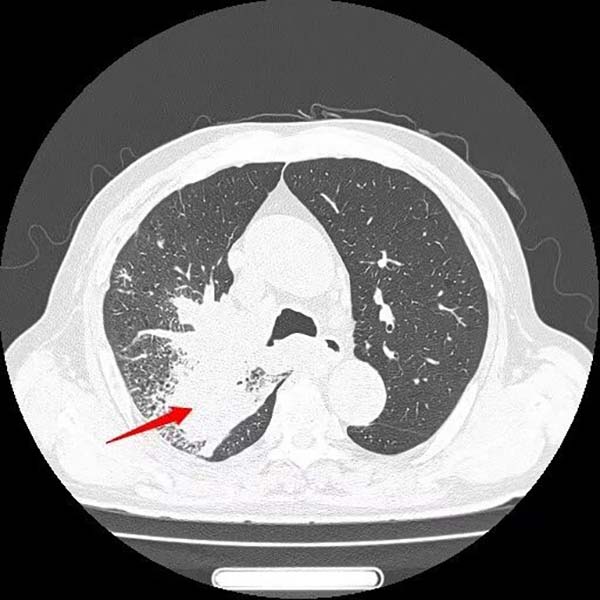

经过一个周期的治疗后,患者喘憋、咳嗽等呼吸道症状明显缓解,复查影像显示右肺上叶肿物显著缩小,疗效评估良好。这一结果让患者及家属重拾治疗信心,也为下一阶段治疗奠定了基础。